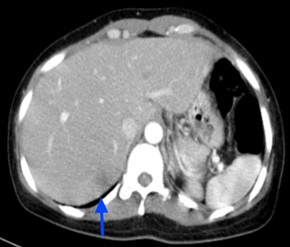

Hình 12: Hình ảnh CT ổ bụng sau 6 tháng điều trị: Khối nhu mô gan hạ phân thùy S7 giảm tỷ trọng, ngấm thuốc kém sau tiêm, Kích thước tổn thương giảm dần qua các đợt điều trị: và 15mm (mũi tên xanh)